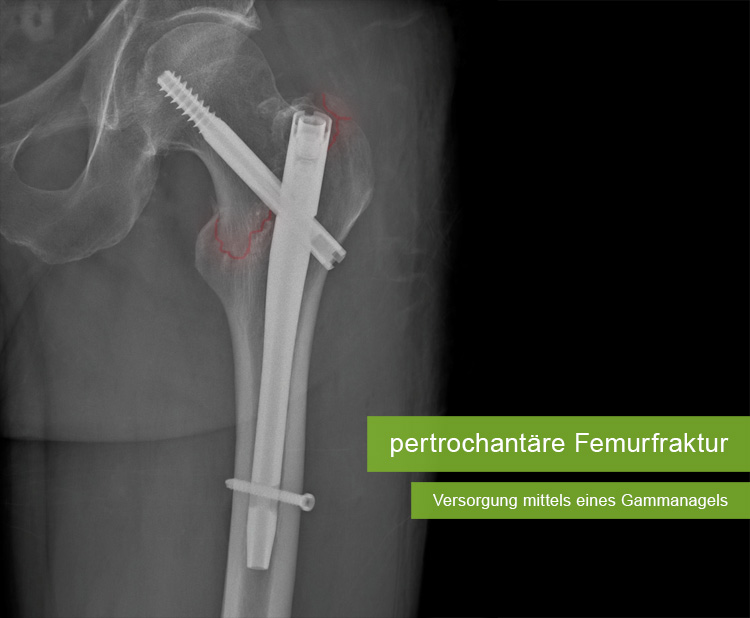

In einer angenehmen und kollegialen Arbeitsatmosphäre werden Sie die Diagnostik und Behandlung vieler Erkrankungen und Verletzungen des Haltungs- und Bewegungsapparates kennenlernen.

Sie nehmen an unseren Besprechungen und Röntgenkonferenzen teil, werden in die Stationsarbeit integriert, erwerben Kenntnisse hinsichtlich der erforderlichen Dokumentation von der Aufnahme des Patienten bis zu seiner Entlassung, assistieren bei verschiedenen orthopädischen und unfallchirurgischen Operationen, können in unseren Sprechstunden hospitieren und sich auch an unseren Fortbildungsveranstaltungen beteiligen. Zum Selbststudium steht ihnen die entsprechende Fachliteratur zur Verfügung.